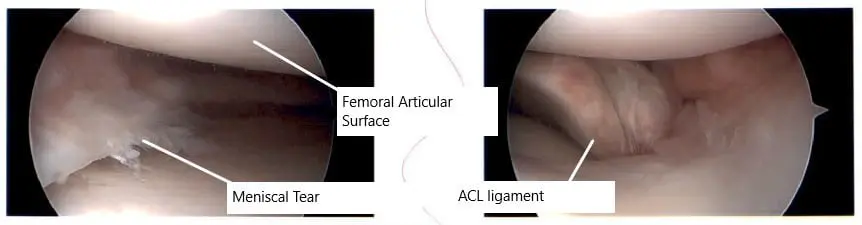

Intraoperative arthroscopic image of the left knee.

A lateral entry portal was made and an arthroscope was introduced into the knee joint. There was no osteochondral lesion of the patellofemoral joint, medial condyle, lateral condyle. Examination of the medial meniscus showed a mid body oblique vertical tear of the medial meniscus along with a tear of the posterior horn of the medial meniscus.

There was an ACL tear, which was not repairable due to it being midsubstance. There was a lateral meniscus tear along with the mid substance and anterior body of the lateral meniscus, which was flipped inside.

Intraoperative picture showing knee arthroscopic surgery.